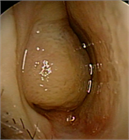

1. 鼻閉感は鼻閉塞に起因することが多いが、上咽頭疾患など鼻腔外の要因でも来し、さらに心身症や萎縮性鼻炎など、閉塞性の病変がなくても生じ得る。